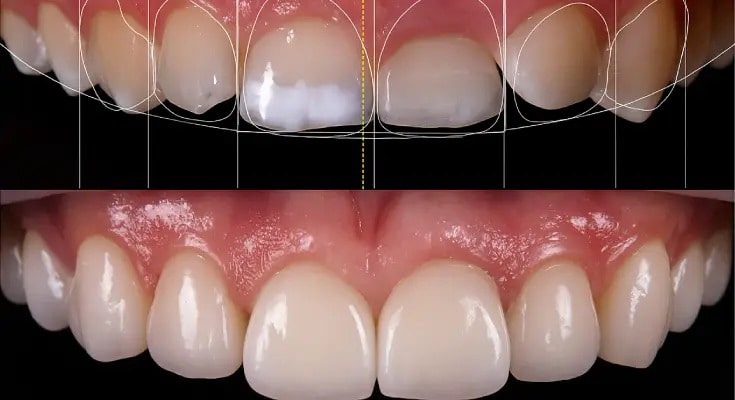

برای رسیدن به یک لبخند زیبا، بدون اینکه به سلامت دندان ها آسیبی برسد، باید به یک دندانپزشک ترمیمی و زیبایی ماهر و باتجربه مراجعه کرد؛ پزشک متخصص، وضعیت دهان و دندان هایتان را بررسی می کند و بهترین روش درمانی را پیشنهاد می دهد. برای مشخص کردن بهترین روش درمان، فرم صورت، رنگ پوست، مو، چشم و …، تناسب عوامل صورت و لبخند، فرم دندان ها، فرم لب ها، تناسب طول و عرض دندان ها، قوس دندانی و عوامل بسیار دیگری باید به دقت بررسی شوند.

بر اساس شکل، اندازه، رنگ دندان و تناسب آن ها با چهره شخص، دندان پزشک متخصص، طرح لبخند متفاوتی را مشخص می کند.